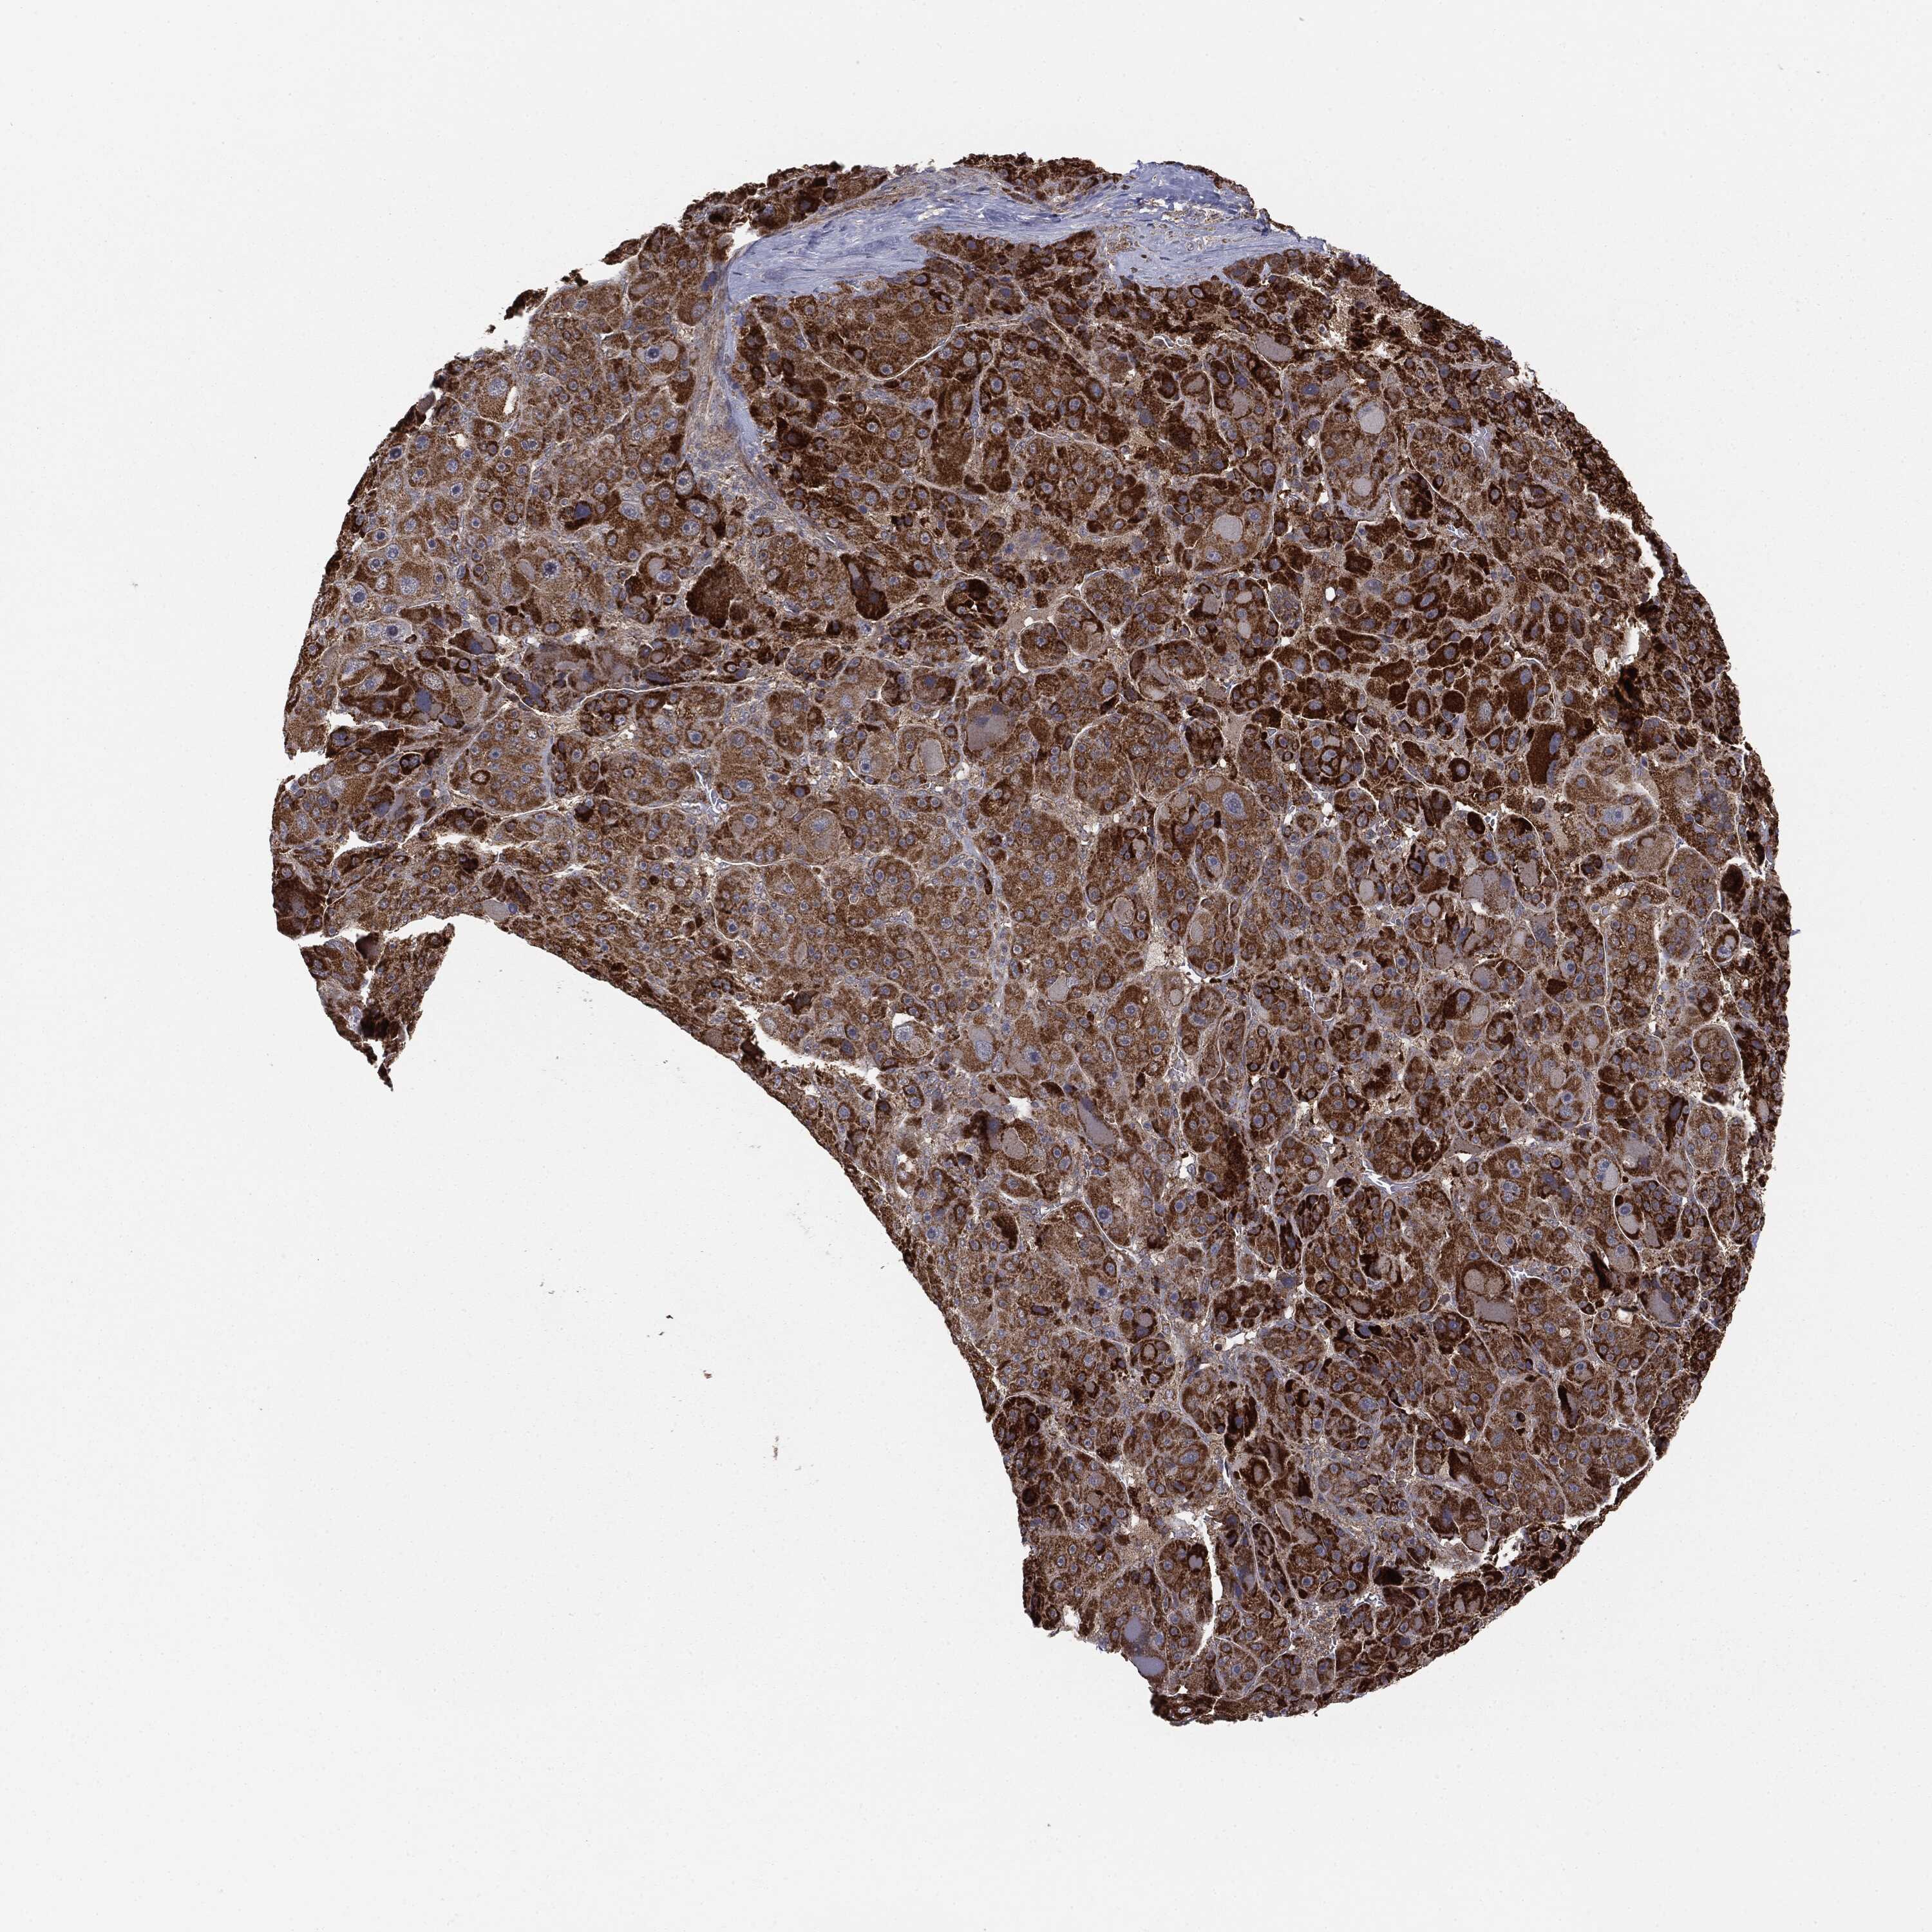

LIVER CANCER - Protein expressioni

A mouse-over function shows sample information and annotation data. Click on an image to view it in a full screen mode. Samples can be filtered based on level of antibody staining by selecting one or several of the following categories: high, medium, low and not detected. The assay and annotation is described here.

Note that samples used for immunohistochemistry by the Human Protein Atlas do not correspond to samples in the TCGA dataset.

Antibody stainingi

Antibody staining in the annotated cell types in the current human tissue is reported as not detected, low, medium, or high, based on conventional immunohistochemistry profiling in selected tissues. This score is based on the combination of the staining intensity and fraction of stained cells.

Each image is clickable and will lead to virtual microscopy that enables deeper exploration of all samples and also displays staining intensity scores, fraction scores and subcellular localization as well as patient and tissue information for each sample.

Carcinoma, Hepatocellular, NOS